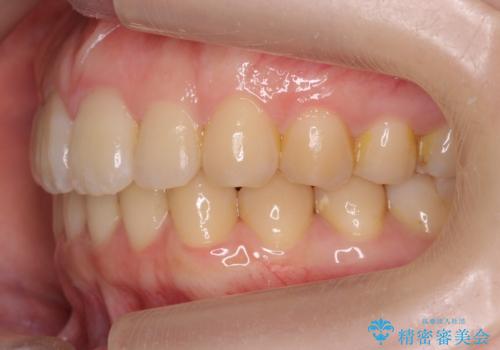

奥歯のかみ合わせも妥協しない インビザライン治療

- 歯のがたつきを主訴に来院。

左右とも奥歯のがたつきがあり、左奥はすれ違っていました。

また、右奥は反対咬合になっていました。

患者様が気づかない範囲で妥協して終わるということをせず、しっかり奥歯に部分矯正を用いて大きな問題を解決してからインビザライン治療に入りました。

下の前歯を一本抜歯しています。(抜歯の本数は最小限にしています。)